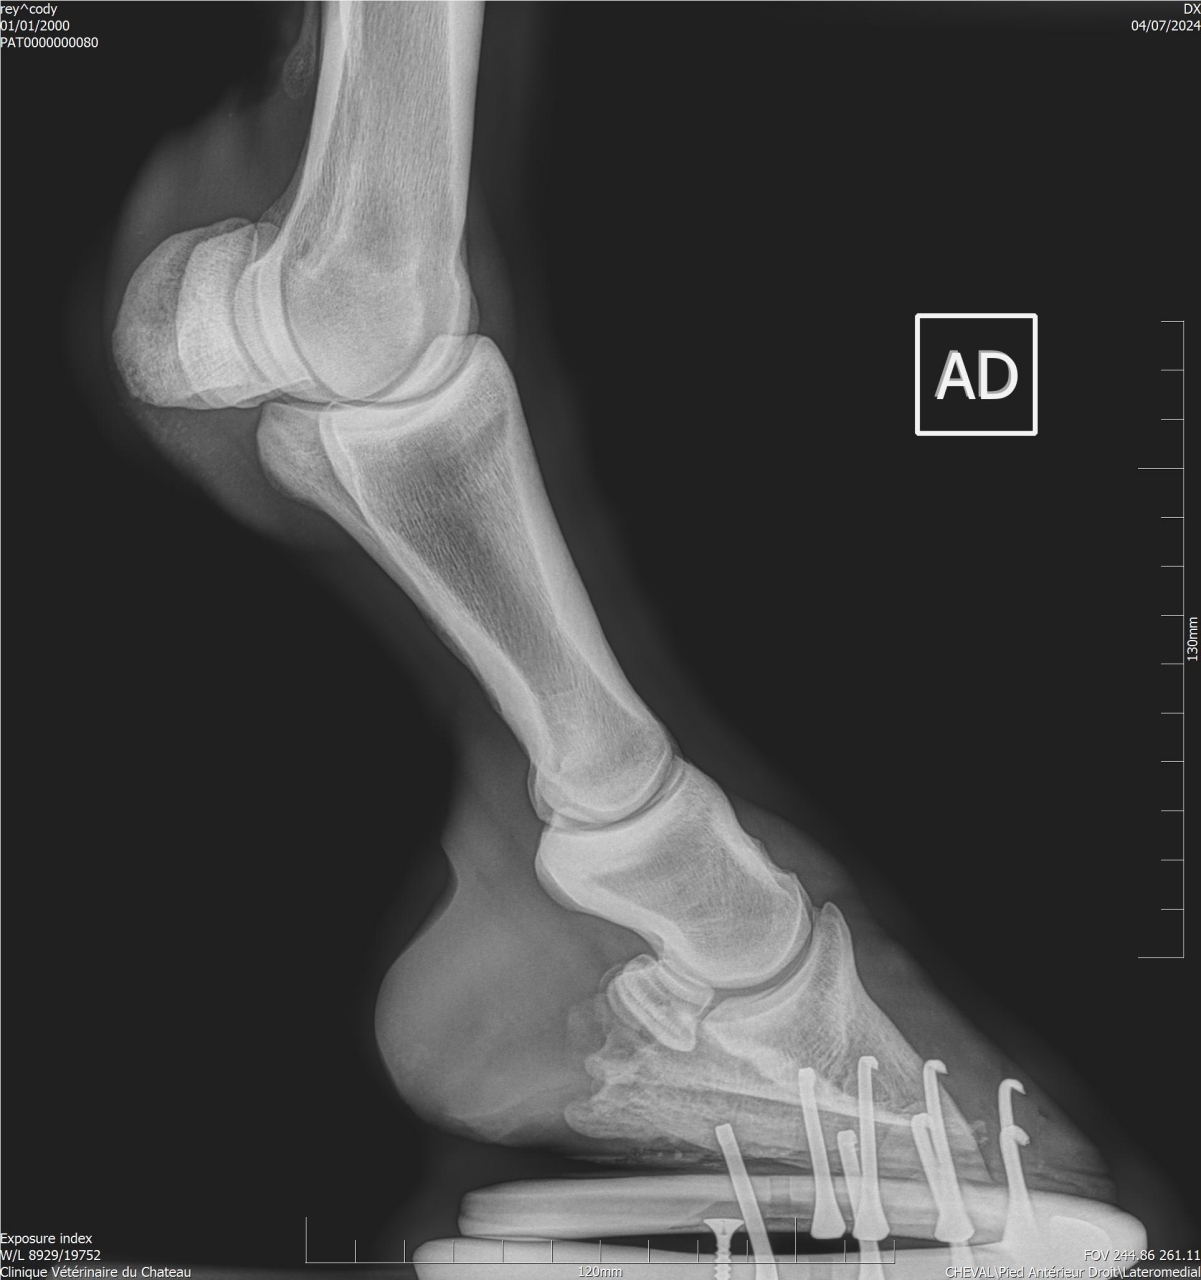

| Dire merci | Je fais un sujet à part pour donner des nouvelles ![]() J’ai fait passer un autre véto pour un 2ème avis. Au début il pensait à un abcès très profond, emplacement détecté avec la pince à sonder. Il a ensuite fait des radios : si j’ai bien compris, la 3ème phalange appuie sur la sole Il y a également de l’arthrose ... Le traitement pour le moment : anti inflammatoires et hipposandales en attendant de pouvoir referrer, et changer de maréchal ferrant. Apparemment il existerait un traitement au laser, le véto va se renseigner. Cody a fait une fourbure l’année dernière, des radios ont été faites à ce moment. J’ai aussi refait des radios de contrôle cette année, il restait une légère bascule de P3. |

| Dire merci | Radios de mai 2023![]() ![]() Radios de juillet 2023 ![]() ![]() Radios d'août 2024 ![]() ![]() |

| Dire merci | Il y a quand même de jolies bascules, il doit pas être bien c'est sûre. Les degrés de bascule t'ont été donnés? Pour moi il y a urgence à trouver un bon maréchal, qui va travailler avec les radios, mais ça va mettre plusieurs mois à "rentrer dans l'ordre" si pas d'autres crises inflammatoires et nouvelles bascules, ça se compte en plusieurs mois voir année. Et malheureusement une surveillance constante. |

| Dire merci | J'ai eu le collègue du véto au téléphone : pas de risque immédiat que la phalange perce la sole il reste 1 cm. La 3ème phalange appuie sur la sole, il y a nécrose. La pointe ne risque pas de casser. Je viens de commander 2 hipposandales Cloud. Il faut que je trouve quelqu'un pour déferrer Cody et éventuellement parer l’autre antérieur. Message édité le 22/11/24 à 20:31 |

| Dire merci | Voici les dernières radios :![]() ![]() ![]() |